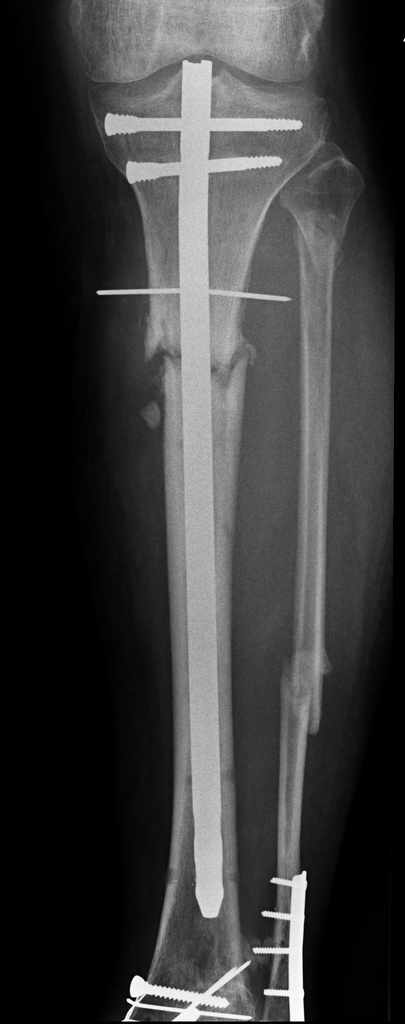

У пациента 55 лет после открытого перелома костей голени остро развилось глубокое нагноение верхней трети голени.

Травма в октябре 2007 года открытый перелом 3 ст - ПХО, наложение стержневого аппарата, остеосинтез ложыжек при поступлении. После заживления ран через 10 дней - закрытый интрамедуллярный остеосинтез без рассверливания. Применялась отклоняющая спица, которая оставлена подкожно для контроля положения проксимального фрагмента. Певичное заживление ран.

Динамизация остеосинтеза через 1,5 месяцев, однако в динамике рентгенологически - признаки формирования ложного сустава. Последние 2 месяца ходьба с полной нагрузкой без клинических жалоб.

5 дней назад без видимой причины подъем температуры, гиперемия по внутренней поверхности в/3 голени, формирование абсцесса. При вскрытии 2 дня назад около 80 мл сливкообразного гноя. Спица удалена (видимо она и была причиной инфицирования), винты нестабильны - также удалены. Гвоздь оставили на месте (пока). Дном гнойной раны явлется кость, зонд доходит до гвоздя. в настоящее вроем рана дренируется выпускниками, количество отделяемого уменьшается.

Вопрос по дальнейшему лечению. Интрамедуллярная фиксация оказалась нестабильной, поэтому рассматриваем 2 варианта:

1. Удаление стержня - переход на ВКДО по Илизарову с промывным дренированием канала.

2. То же, но вместо промывания - интрамедуллярный тонкий стержень с антибиотиком на цементе.